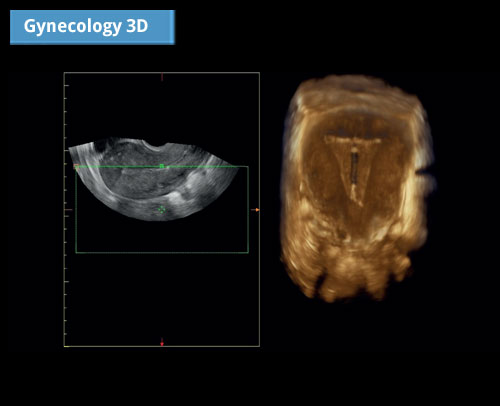

Gynekologie 3D: Vynikající 2D zobrazování a dokonalé vykreslování 3D rekonstrukce.